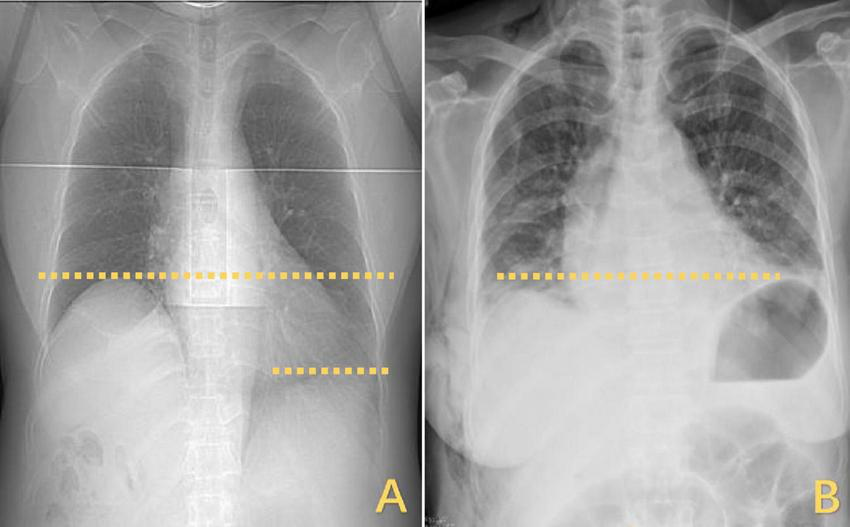

FIGURE 4

Changes in the horizontal position of the right diaphragm before and after DP. (A) The right diaphragm was significantly raised compared to the left diaphragm, which was elevated by approximately three vertebral levels. (B) Postoperatively, both diaphragms returned to the same level. DP, diaphragmatic plication.

However, the patient’s treatment process was not very smooth, and the patient experienced twists and turns. The treatment of BCS began with an interventional approach using a balloon to dilate and shape the stenotic IVC. The patency of the IVC was restored after balloon inflation (Figure 3A), but the original stenosis returned immediately after balloon withdrawal, and there was no change in the internal diameter of the stenosis (Figure 3B). There was no benefit from three rounds of balloon inflation. Postoperative chest radiographs showed a marked elevation of the right diaphragm in contrast to the left diaphragm, which was elevated by approximately three vertebral levels, consistent with a diagnosis of DE (Figure 4A). Subsequently, ultrasound examination of diaphragmatic mobility revealed that during calm breathing, the right diaphragm amplitude was 0.20–0.47 cm and did not change significantly; the left diaphragm amplitude was 2.4 cm; which was consistent with the diagnosis of right DE (Figure 5). Tumors of thoracic and mediastinal origin and those caused by inflammation were ruled out by positron emission tomography/computed tomography (PET/CT). Based on these findings, the CT images were further reviewed. It was suggested that the elevation of the diaphragm led to liver transposition and torsion of the HV at the confluence of the IVC. This approach helped to clarify the distortion of the IVC despite several interventional balloon dilatations due to the external force exerted by liver traction. To prevent further elevation of the diaphragm from worsening the obstruction, DP was recommended by thoracic surgeons. However, the efficacy of this procedure for treating BCS is inconclusive and has not been reported in the literature. Nonetheless, DP minimally invasive, and even if it is ineffective, it does not increase the difficulty of open surgery.

The right diaphragm dropped to almost the same level as the left diaphragm on the third day after DP (Figure 4B). The patency of the IVC stenosis was restored with by increasing the internal diameter to 1.2 cm (Figure 2B). And the flow rate returned to normal (Figure 2D). The patient’s blood ammonia level decreased to 66.4 μmol/L. She had a thoracic close drainage removed on the third postoperative day, had no postoperative complications, and was discharged on the fourth postoperative day. At 1 year postoperative follow-up, ultrasonographic evaluation of IVC revealed a maximum diameter of 1.46 cm, with a mean flow velocity of 0.5 m per second and peak velocity of approximately 1 m per second (Figure 7). Serial blood ammonia monitoring demonstrated persistently normal levels throughout the follow-up period (Figure 8).